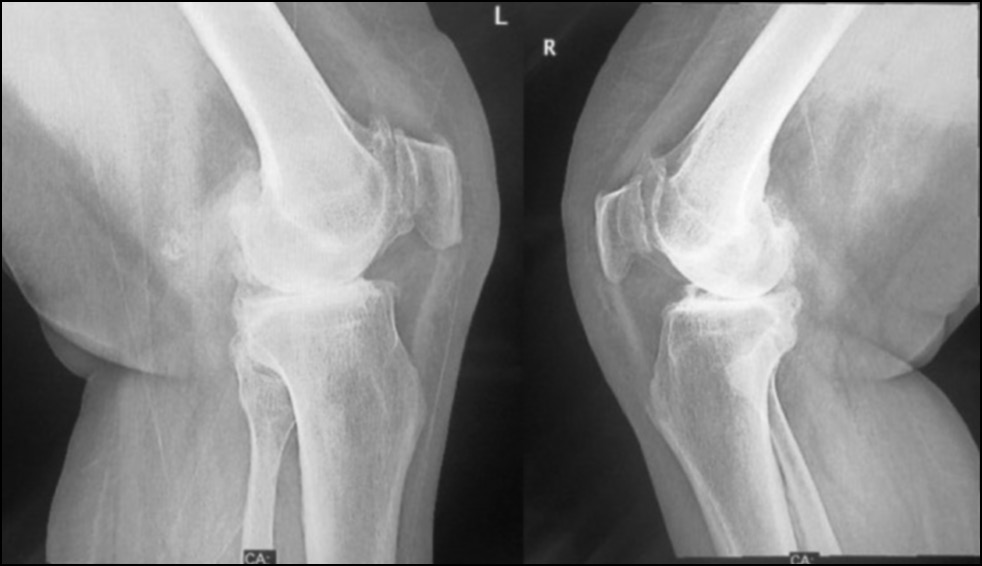

CASE 1. PATIENT 16

Age: 64 years.

Sex: Female.

Diagnosis: Bilateral advanced knee osteoarthritis.

Procedure: Bilateral simultaneous knee arthroplasty.

Associated illnesses: Hypertension.

Postoperative follow-up: No postoperative complications were encountered.

Length of hospital stay: 6 days.

Radiological assessment (Fig. 11–14)

Fig. 11. Ap preoperative x-ray showing bilateral knee osteoarthritis.

Рис. 11. Предоперационная рентгенограмма с двусторонним остеоартритом коленного сустава.

Fig. 12. Lateral preoperative x-ray right and left knees showing osteoarthritis.

Рис. 12. Предоперационная боковая рентгенограмма правого и левого колена с признаками остеоартрита.